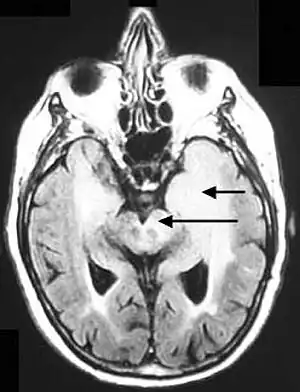

Hemispheric gyriform hyperintense signal variations -

Axial fluid-attenuated inversion recovery MRI image demonstrating tumor-related infiltration involving lenticular nuclei (Arrow). -

Axial fluid-attenuated inversion recovery MRI image demonstrating tumor-related infiltration involving both temporal lobes (Short arrow), and the substantia nigra (Long arrow).